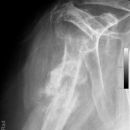

Knöcherner Supraspinatussehnenausriss